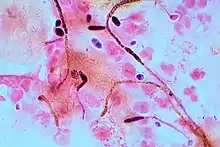

Diagnosis of a yeast infection is confirmed either via microscopic examination or culturing. For identification by light microscopy, a scraping or swab of the affected area is placed on a microscope slide. A single drop of 10% potassium hydroxide (KOH) solution is then added to the specimen. The KOH dissolves the skin cells, but leaves the Candida cells intact, permitting visualization of pseudohyphae and budding yeast cells typical of many Candida species.

For the culturing method, a sterile swab is rubbed on the infected skin surface. The swab is then streaked on a culture medium. The culture is incubated at 37 °C (98.6 °F) for several days, to allow development of yeast or bacterial colonies. The characteristics (such as morphology and colour) of the colonies may allow initial diagnosis of the organism causing disease symptoms.[58] Respiratory, gastrointestinal, and esophageal candidiasis require an endoscopy to diagnose.[28][59] For gastrointestinal candidiasis, it is necessary to obtain a 3–5 milliliter sample of fluid from the duodenum for fungal culture.[28] The diagnosis of gastrointestinal candidiasis is based upon the culture containing in excess of 1,000 colony-forming units per milliliter.[28]